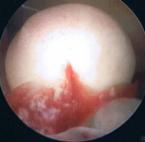

Schließlich ist die Ultraschalluntersuchung auch in der Lage, zur frühzeitigen Entdeckung von Krebserkrankungen beizutragen, wie auf dem unteren Beispiel: links wieder das Ultraschallbild (diesmal zwei Aufnahmen in unterschiedlichen Ebenen, die hellen Strukturen sind die verdächtigen Gewebsanteile), rechts die Veränderungen bei der anschließenden Gebärmutterspiegelung: polypöse Strukturen mit Übergang in einen Gebärmutterkörperkrebs.